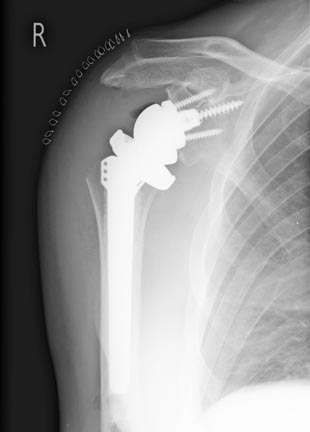

SchulterprotheseIst nur der Humeruskopf betroffen, wird hierbei lediglich die Oberfläche mit einem Titanimplantat ersetzt. Sollten beide Gelenkpartner betroffen sein, besteht die Indikation für eine anatomische Totalendoprothese. Da das Schultergelenk das Gelenk mit dem umfangreichsten Bewegungsumfang ist, muss bei der Wahl der Prothese auch die gelenkführende Muskulatur beachtet werden. Ist die Rotatorenmanschette (= Muskel-Sehnen-Kappe der Schulter) defekt, hilft nur noch eine sogenannte Inverse Prothese, bei der das Bewegungszentrum des Schultergelenkes so verlagert wird, dass die noch intakte Muskulatur die weitgehende Funktion der Endoprothese übernimmt.

Nach einem endoprothetischen Gelenksersatz ist nach einer Rehabilitation von ca. 3 Monaten mit einer weitgehenden Schmerzfreiheit zu rechnen.